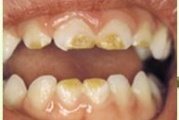

Fluoroos

Fluoroosi

Hammaste defektid